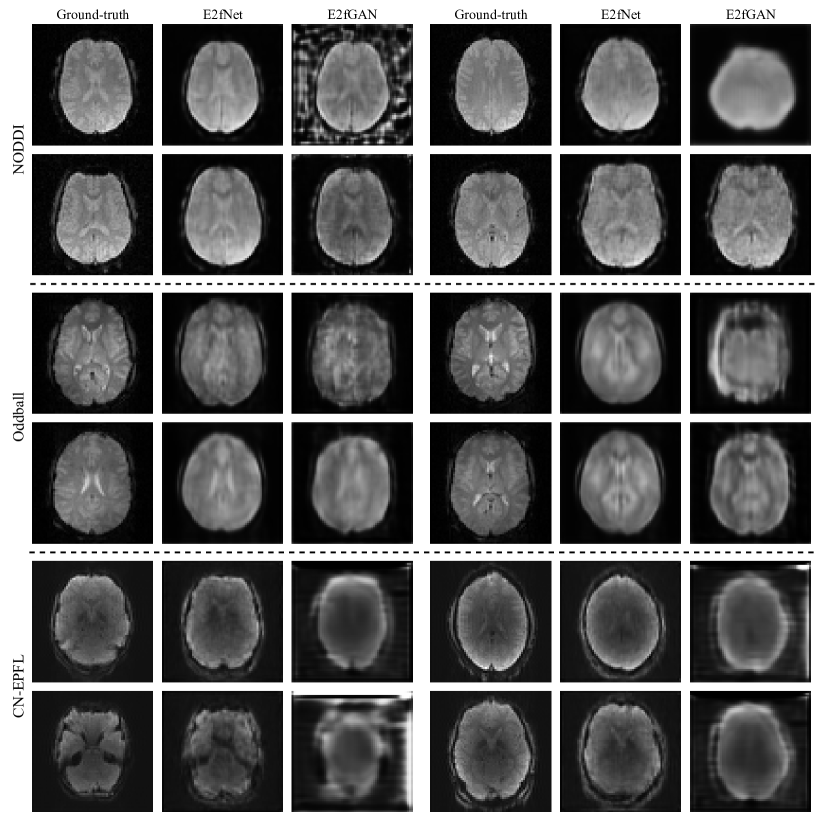

Refer to caption

Figure 2: Visual comparison of the generated fMRI by E2fNet and E2fGAN models on the NODDI, Oddball, and CN-EPFL datasets.

To provide a more comprehensive evaluation, we compared E2fNet with the GAN-based E2fGAN model, which uses E2fNet as the generator. Fig. 2 presents a visual comparison of E2fNet and E2fGAN across the three datasets. During the experiments, we observed that training the GAN model was often unstable, leading to unexpected outputs (Fig. 2, first row of the NODDI and Oddball datasets, first example in the second row of the CN-EPFL dataset). This instability contributed to E2fGAN’s lower SSIM and PSNR scores compared to E2fNet. Nevertheless, in some cases, E2fGAN produced visually sharper fMRI volumes. Future work could explore improvements by adopting more robust GAN training strategies.

It is important to note that SSIM and PSNR metrics may be sometimes less reliable when evaluating small or blurry images. For instance, while E2fGAN frequently generated oversmoothed and less detailed results on the CN-EPFL dataset, it still achieved seemingly reasonable SSIM and PSNR scores. We believe developing better similarity metrics could help address this limitation. There is still room for improvement, and we plan to investigate these aspects in future work.